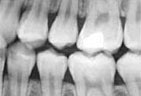

| We use state of the art digital X-rays and digital cameras to help with an accurate diagnosis of any concerns. Digital X-rays use less radiation to get a diagnostic picture of your teeth and they help the environment by eliminating the use of chemicals to process the film. | |